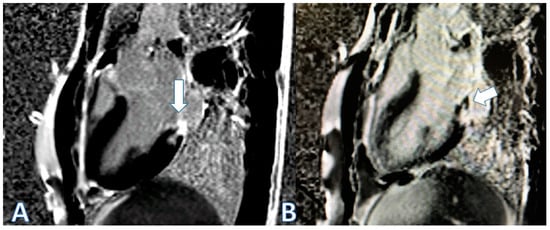

| CMR at hospitalization | LGE of both pericardial leaves and foci of late subepicardial enhancement on the basal inferolateral, lateral, and inferior walls | LGE at the level of the pericardial leaves and a basal inferolateral subepicardial focus | Edema and LGE in the lower-middle, inferolateral, and anterolateral segments | Edema and LGE at the anterolateral, basal-mid inferolateral and basal inferior segments, and intramyocardial in the mid-inferoseptal and apex segments |

| Control CMR at 6–9 months | Persistence of LGE on the inferolateral wall | - | LGE in the inferolateral and anterolateral walls | LGE intramyocardial and subepicardial at inferolateral, anterolateral, and inferoseptal walls (reduced extent) |